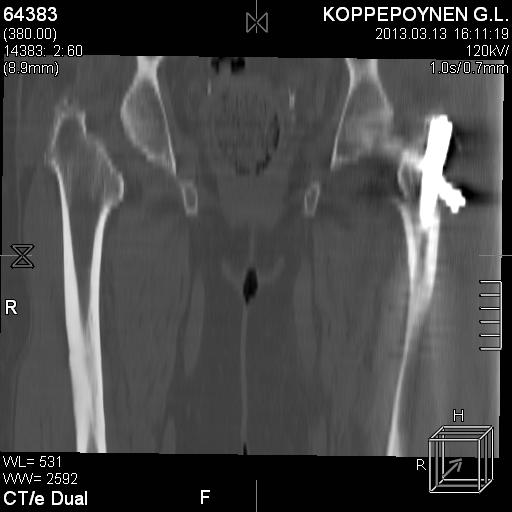

Делали КТ после операции.

|

Отправитель: Alexander Chelnokov 14 Октябрь 2013, 03:21

Непонятно, на какой вопрос с помощью КТ хотели получить ответ? IMHO это было ненужное исследование, все проблемы были видны на обычном снимке. А что на второй проекции? Где аксиальная или профиль?

есть КТ после операции. у пациентки направление введения стержня совпадает с направлением большого вертела, однако большой вертел расколот на 2 отломка. Задний отломок лежит по оси, передний отломом "отошел" и создается впечатление неправильного введения стержня. Динамизации у пациентки не было... Привезут снимки после операции, скину